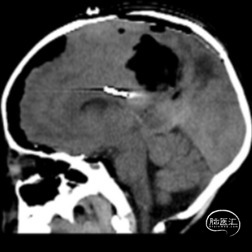

双侧额顶叶中线旁脑实质内团片状异常信号影,呈明显花环状强化,累积脑膜及胼胝体压部,性质待定,恶性胶质瘤?

本例患儿肿瘤位于双侧额顶叶,大脑镰旁,增强扫描呈明显环形强化,提示肿瘤血运丰富。患儿年龄小,体重低,相对血容量少,如何控制术中出血是手术成功的关键。而术后肢体瘫痪或瘫痪加重是手术的主要并发症,中央沟静脉损伤、胼周动脉损伤、中央沟局部皮层损伤、癫痫、血肿以及脑水肿加重是其常见原因。术前脑血管造影有助于判断肿瘤与周围血管、组织的位置关系,明确上失状窦有无闭塞,对手术的切口设计有重要的参考价值及避免术中损伤不易发现的血管及组织。

非典型畸胎瘤样/横纹肌样瘤( AT /RT) 是发生在儿童中枢神经系统的少见的具有极大侵袭性的恶性肿瘤,在儿童中枢神经系统肿瘤中发病率极低。CT平扫多表现为混杂密度,也可等或稍高密度,呈不均匀或均匀强化,瘤内常可见囊性变及瘤周低密度水肿带。MRI扫描T1加权像为低信号,T2加权像为等信号或高信号,肿瘤实质与灰质信号相似或稍高,增强扫描可见中等至明显 增强,等信号时可能与肿瘤细胞密集,细胞核比例大而含水量相对较少有关。AT /RT是原发于中枢神经系统、好发于儿童、极其少见、侵袭性极高的胚胎性肿瘤,临床表 现及影像学无特异性,确诊有赖于组织病理。最大限度的安全切除,并辅以放化疗,可改善患者预后,但总体预后仍然很差。